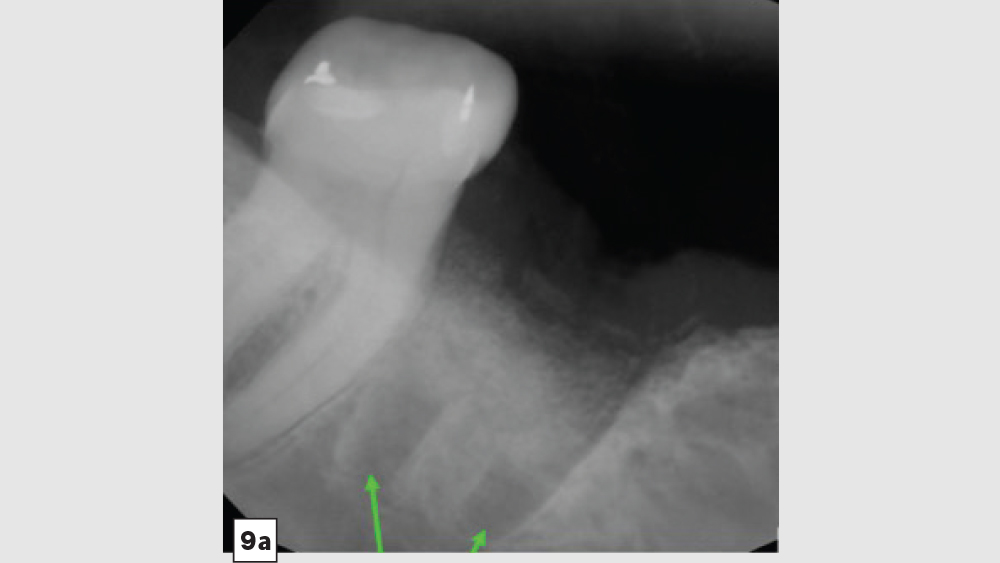

The most common complication from socket grafting techniques is inadequate bone graft fill (Figs. 9a, 9b). Care should be exercised to add bone in small increments, especially to ensure that bone is placed in the apical one-third of the socket. A bone packer should be used with good condensation to avoid air spaces. Additional complications include overfilling of the graft material (Fig. 10). Bone graft material should be placed at the level of the bony crest to allow space for the membrane. If excess bone graft material is condensed above the bone crest, delayed healing will occur.

Figure 9a

Figures 9a, 9b: Inadequate socket grafting with large voids in apical one-third (9a), inadequate bone fill with resultant air space (9b).